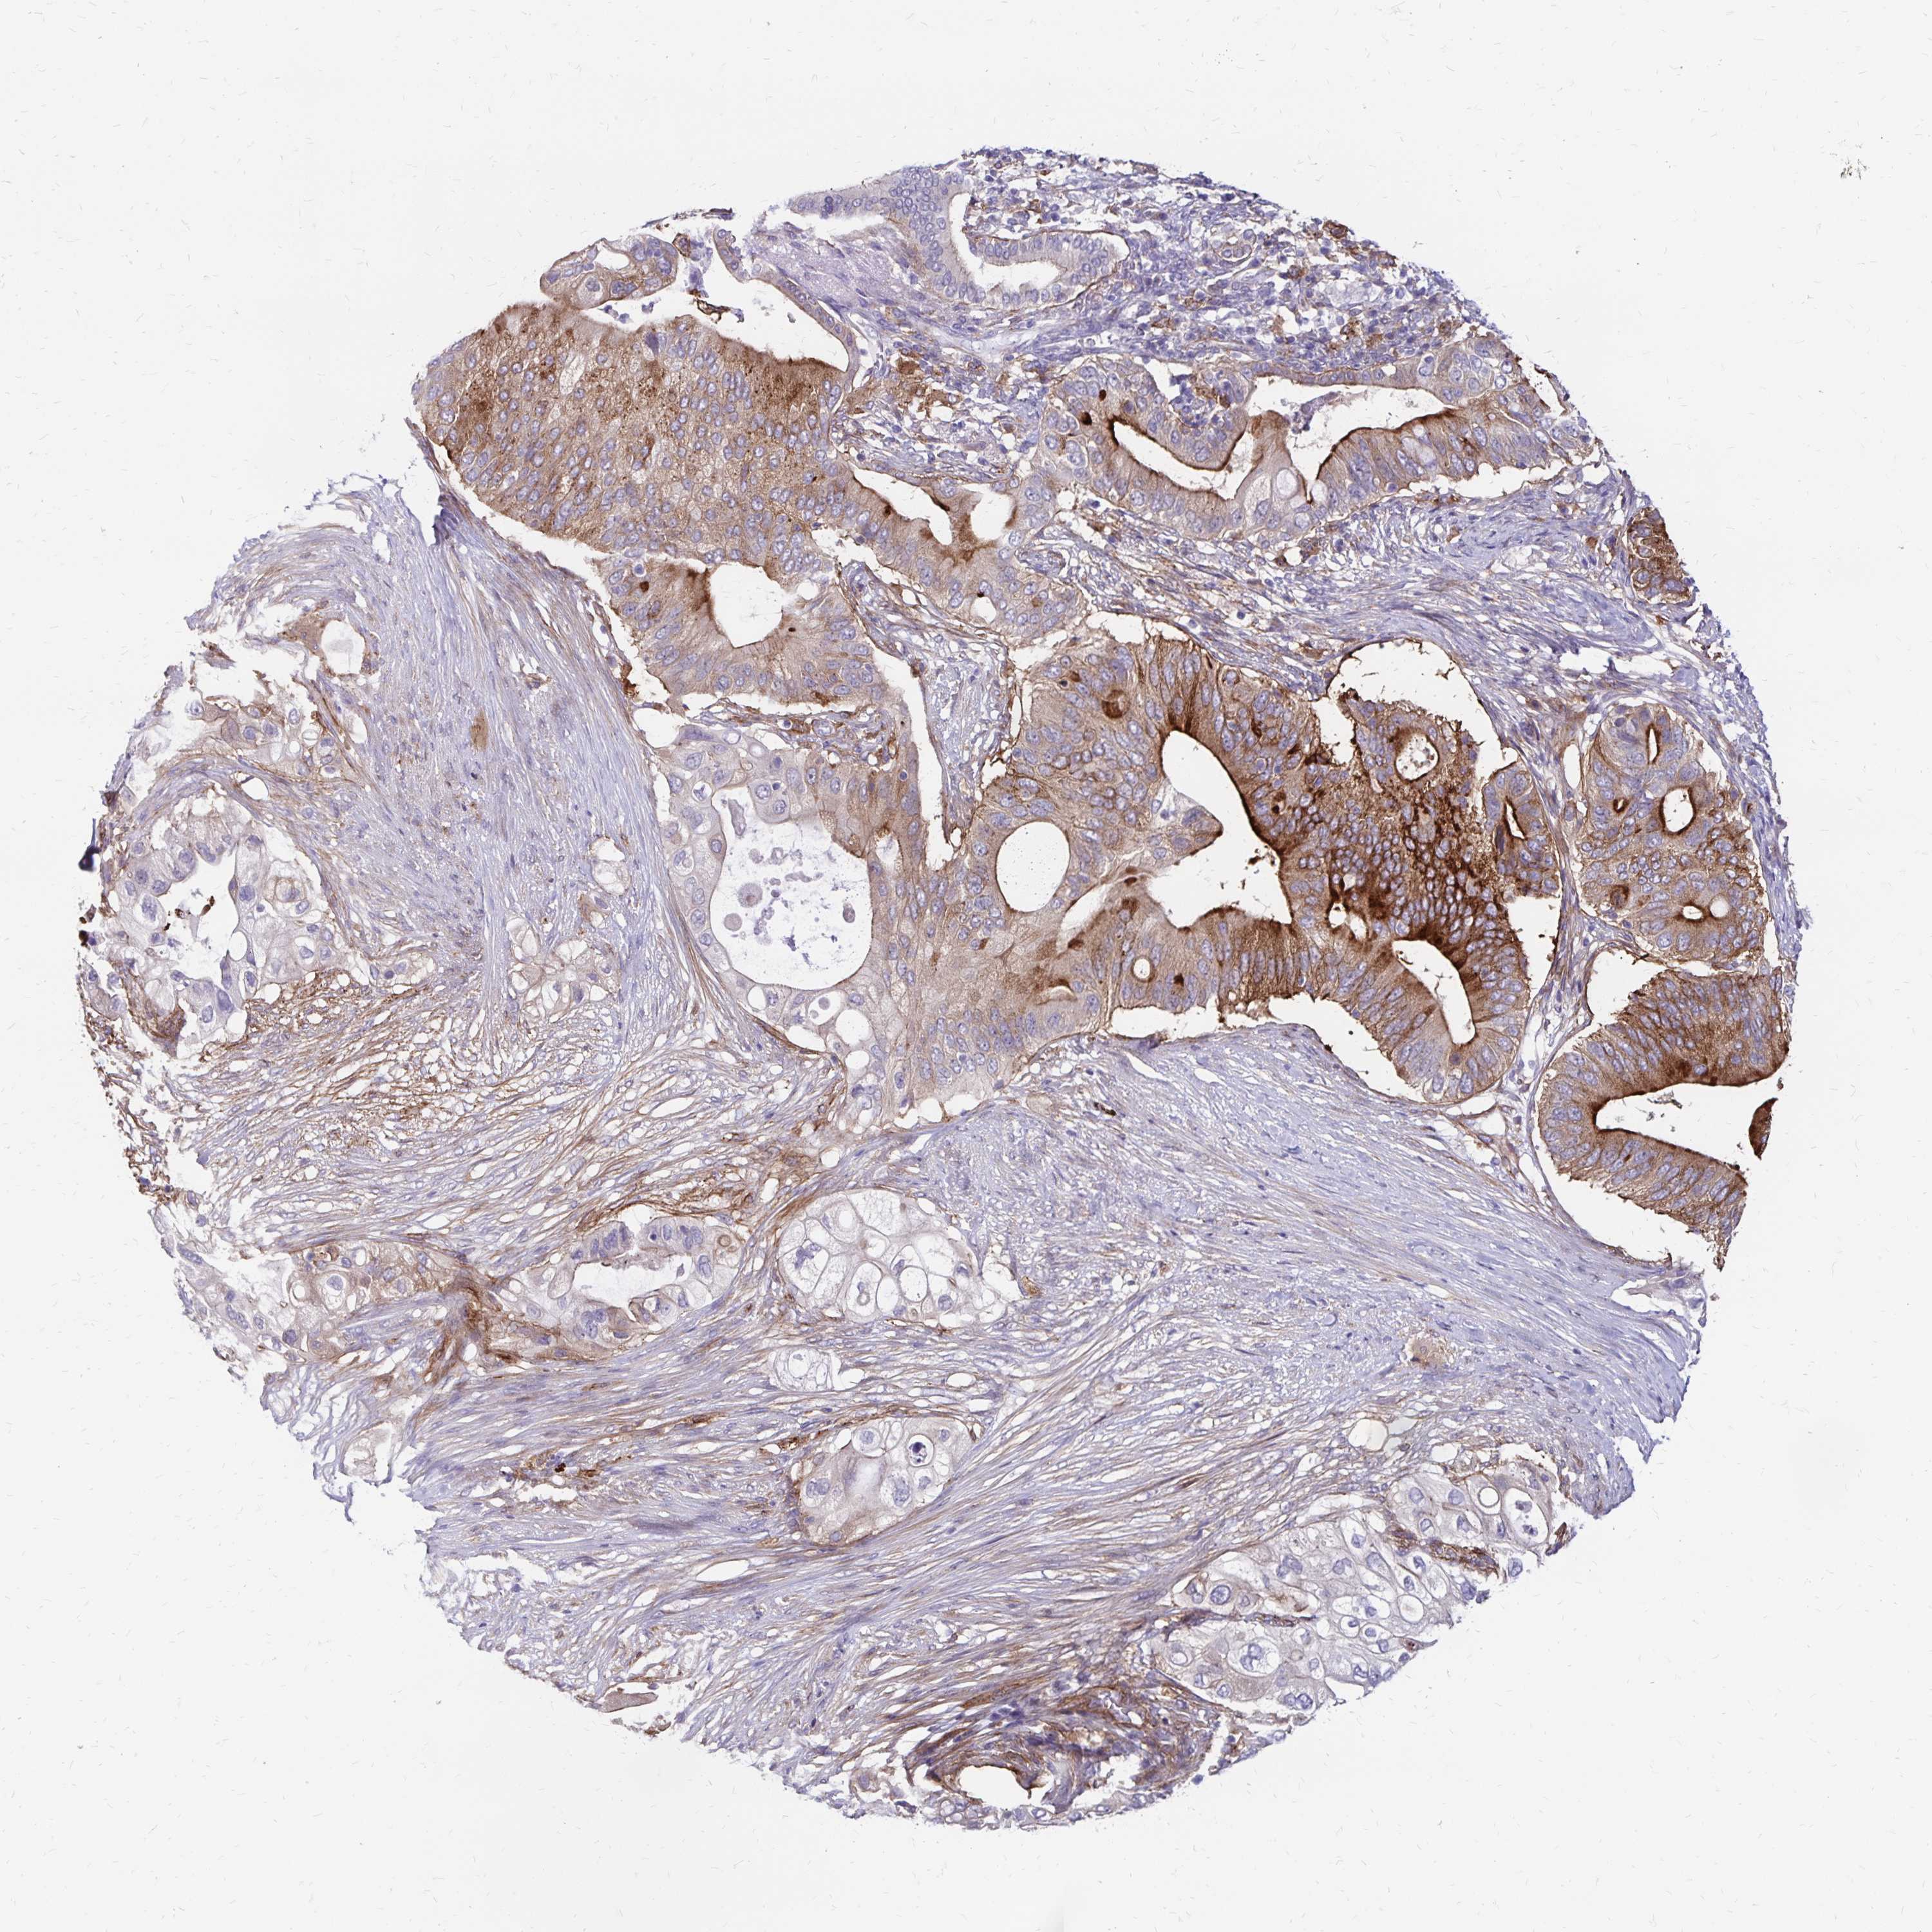

PANCREATIC CANCER - Protein expressioni

A mouse-over function shows sample information and annotation data. Click on an image to view it in a full screen mode. Samples can be filtered based on level of antibody staining by selecting one or several of the following categories: high, medium, low and not detected. The assay and annotation is described here.

Note that samples used for immunohistochemistry by the Human Protein Atlas do not correspond to samples in the TCGA dataset.

Antibody stainingi

Antibody staining in the annotated cell types in the current human tissue is reported as not detected, low, medium, or high, based on conventional immunohistochemistry profiling in selected tissues. This score is based on the combination of the staining intensity and fraction of stained cells.

Each image is clickable and will lead to virtual microscopy that enables deeper exploration of all samples and also displays staining intensity scores, fraction scores and subcellular localization as well as patient and tissue information for each sample.

Antibody HPA055338

Antibody HPA056015

Staining

High

Medium

Low

Not detected

Intensity

Strong

Moderate

Weak

Negative

Quantity

>75%

75%-25%

<25%

None

Location

Nuclear

Cytoplasmic/membranous

Cytoplasmic/membranous,nuclear

Adenocarcinoma, NOS